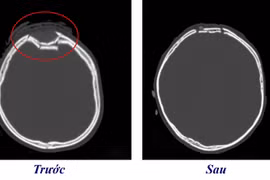

Mũ bảo hiểm lưỡi trai vỡ găm trực tiếp vào xương sọ nam thanh niên 23 tuổi

Việc sử dụng mũ bảo hiểm không đạt chuẩn có thể tăng nguy cơ chấn thương vùng mặt, mắt mũi, xương vùng hàm mặt.